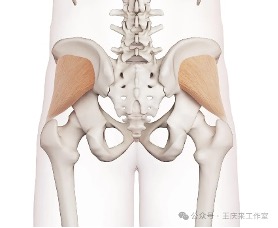

腰痛?屁股痛?你分清楚吗?

腰痛?屁股痛?你分清楚吗?腰痛?屁股痛?你分清楚吗?通常提及腰痛,大家的第一反应都是腰椎间盘突出或者腰肌劳损。但其实在腰部的附近,还有一个常常被忽视的地方——骶髂关节,它的病变往往会引起腰痛及屁股痛。临床上骶髂关节疼痛 (sacroil…查看详情+